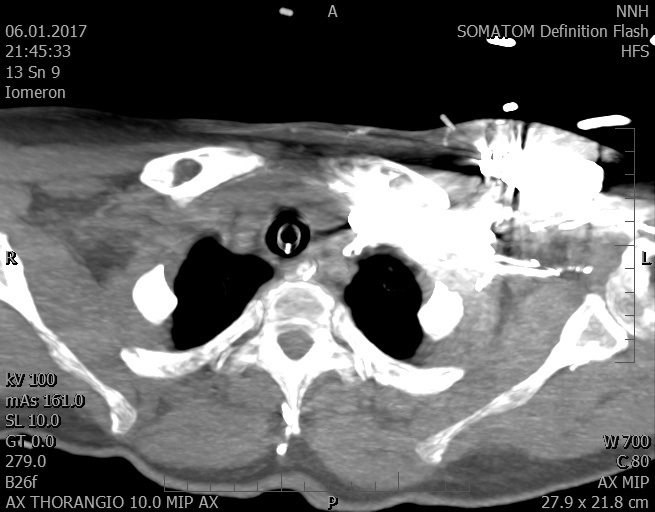

Video 1 - Akutní koronarografie prokázala normální nález na věnčitých tepnách s výjimkou suspekce na lehký spasmus na pravé koronární tepně.Echokardiograficky byla zjištěna těžká dysfunkce dilatované levé komory s nezvětšenou pravou komorou (video 2).

Video 2 - Echokardiograficky byla zjištěna těžká dysfunkce dilatační levé komory s nezvětšenou pravou komorou.Pro nejasnou příčinu zástavy jsme provedli i vyšetření výpočetní tomografií (CT), které vyloučilo plicní embolizaci (série 1 - soubory na konci článku). V den přijetí při přetrvávající oběhové nestabilitě byla nemocná opakovaně defibrilována pro fibrilaci komor se stabilizací rytmu po podání amiodaronu a mesocainu. Dle hemodynamických měření se jednalo o těžký kombinovaný šok. Vstupní laboratorní vyšetření bylo bez větších pozoruhodností. Posléze jsme doplnili anamnézu od příbuzných a zjistili, že pacientka užila do dvou hodin před srdeční zástavou první tabletu amoxicilinu na lehký respirační infekt. Při nevýtěžnosti vstupních vyšetření a nových anamnestických informacích jsme doplnili 14 hodin po kolapsu vyšetření koncentrace tryptázy v séru, která byla extrémně zvýšena (tabulka 2), což nás vedlo k podezření na anafylaxi.